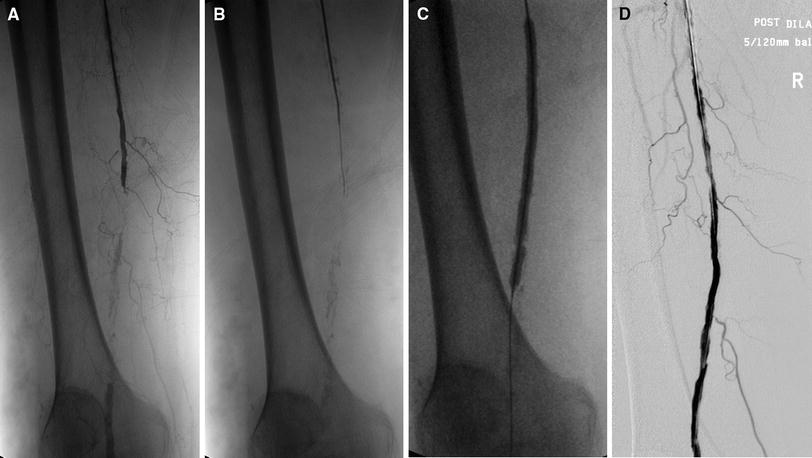

(A) Patient with total occlusion of the right distal superficial femoral artery (SFA)-popliteal artery with severe calcifications, collaterals, and a patent popliteal artery; (B) subintimal passage of the guidewire; (C) subsequent dilatation with a 5 × 120-mm balloon; and (D) final angiographic result